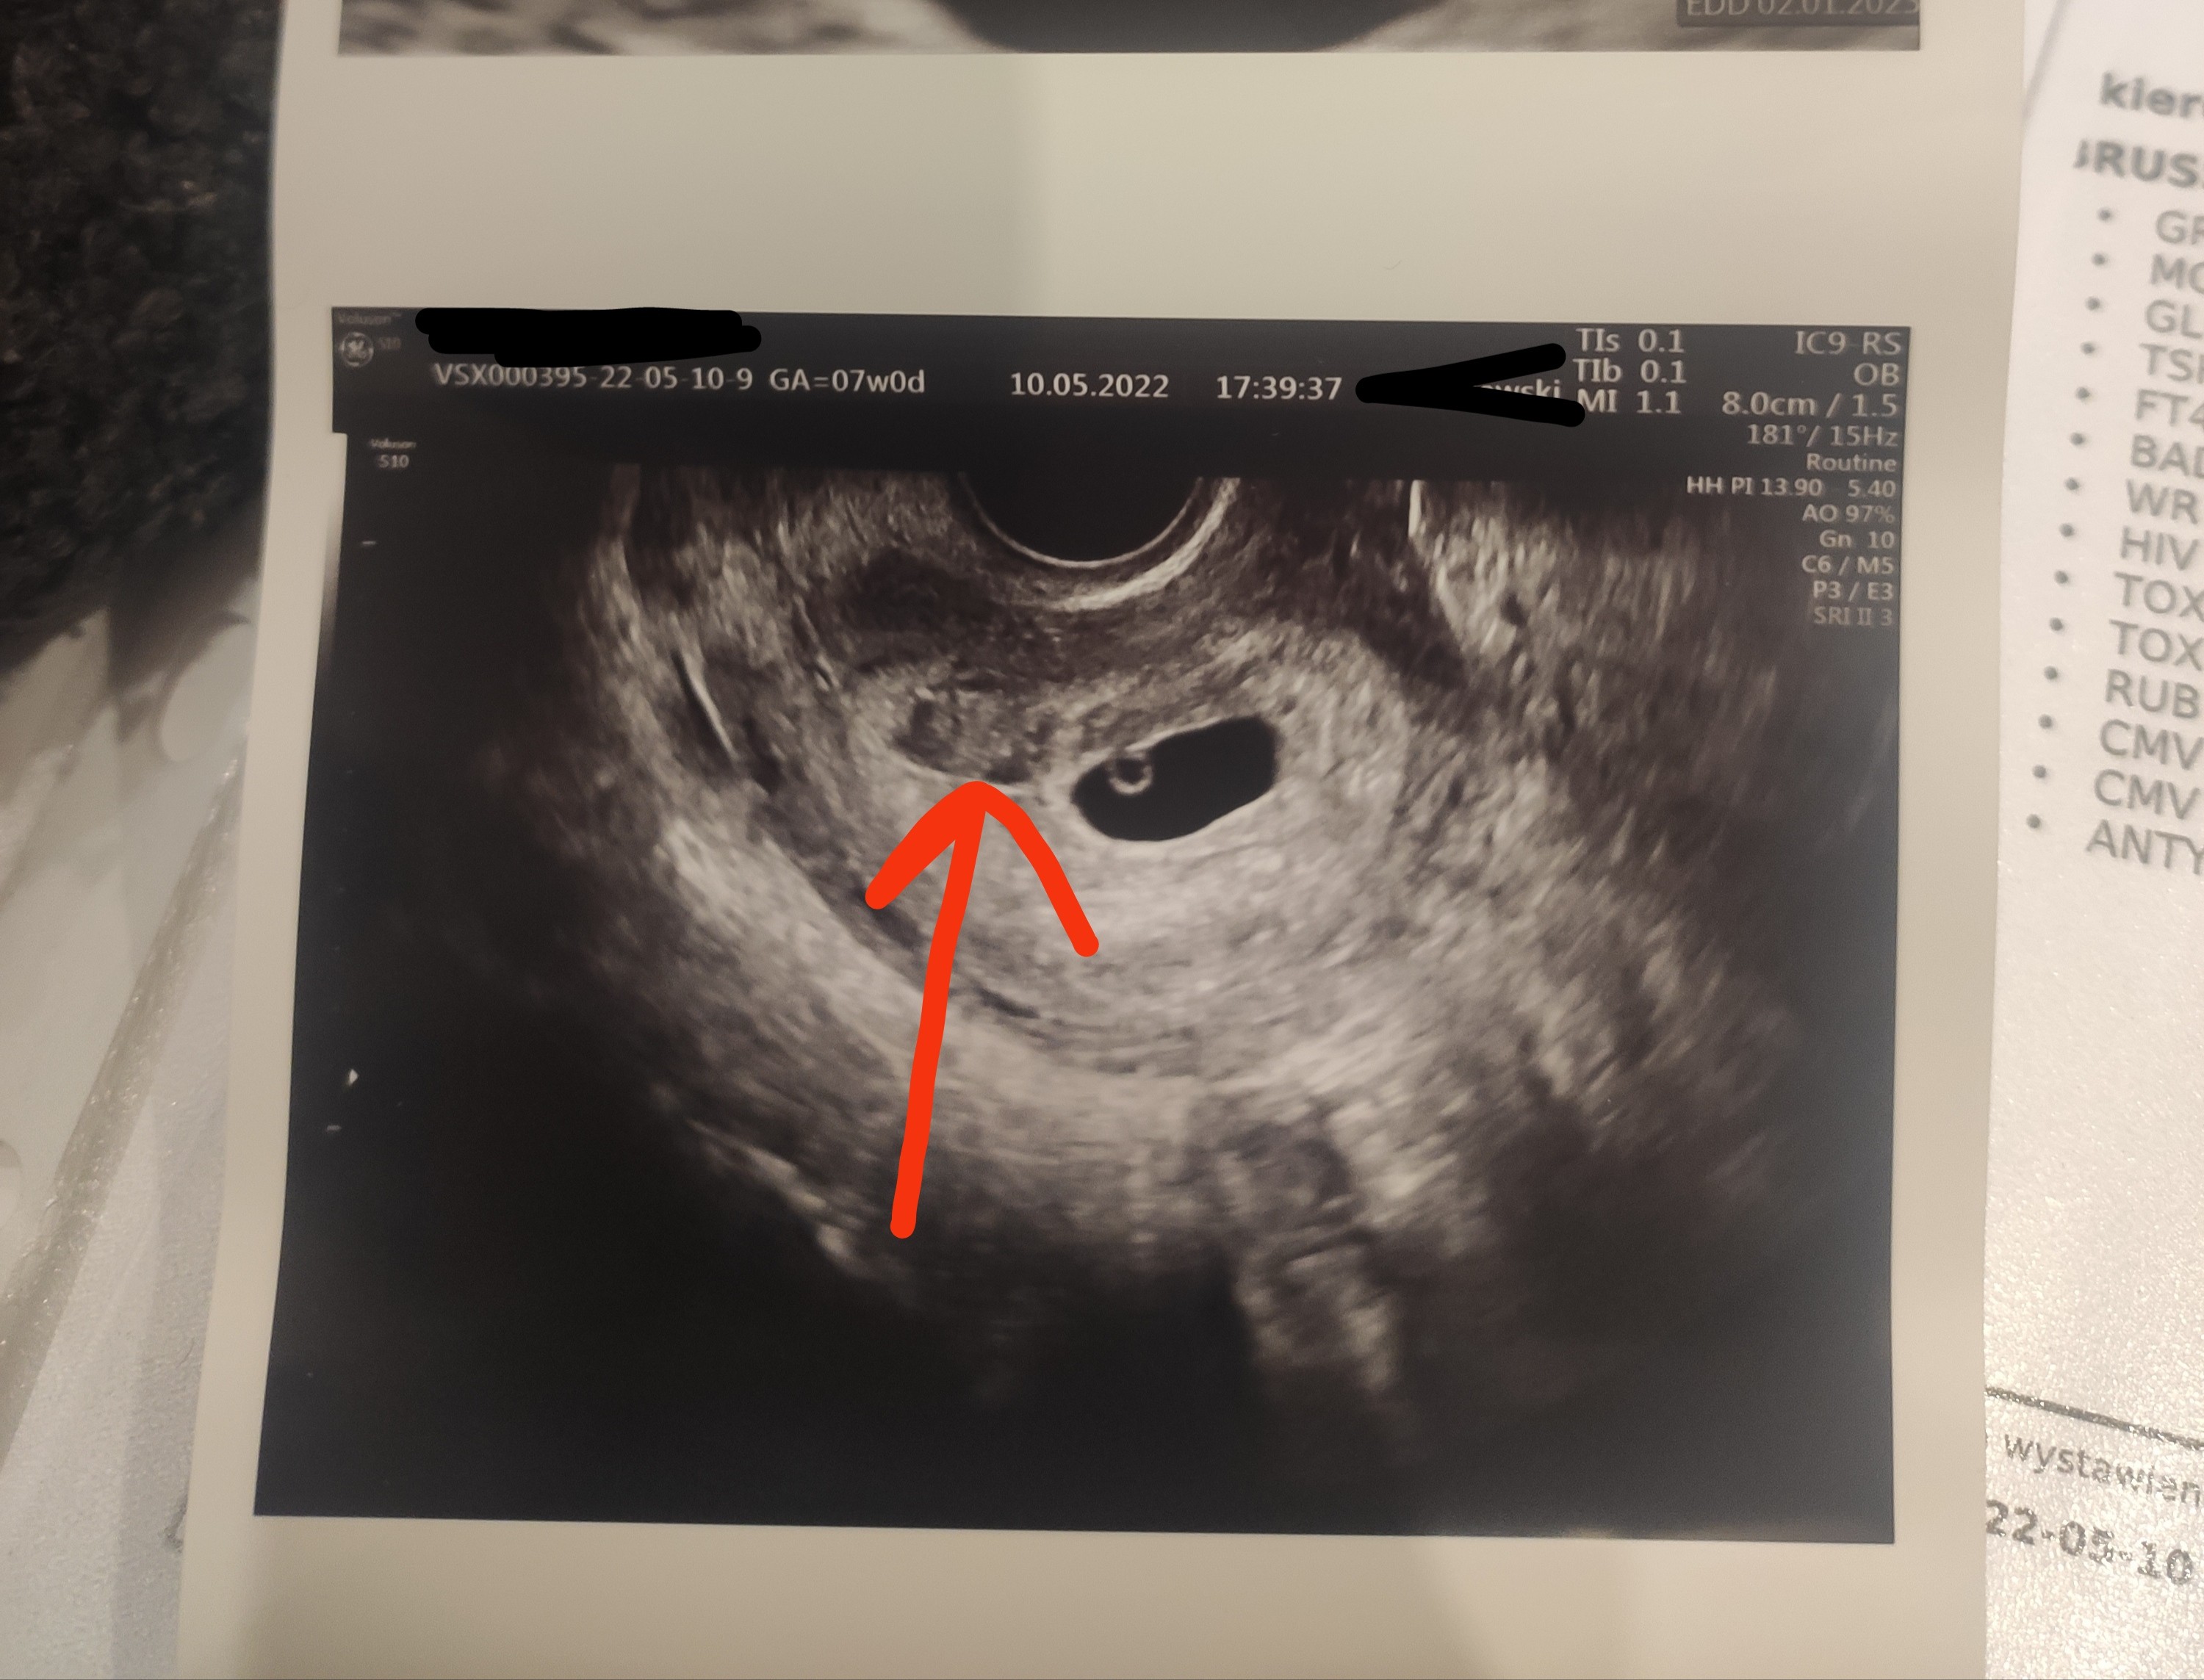

Niby tu jest ten krwiak. No i mam też torbiel na prawym jajniku, co też ponoć jest standardem w ciazy...

Zobacz załącznik 1399909

Jeśli to jest krwiak to ma już zaburzoną echogennosc, wyglada jakby krzepł i sie wchłaniał. I jest malutki, nie przejmowalabym się